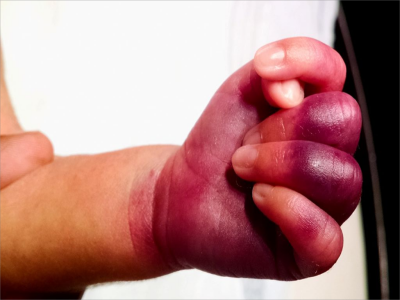

手部

皮肤发紫

暴发性紫癜手部皮肤发紫图

暴发性紫癜的重症患者手部皮肤全部变为深紫色,伴有肿胀、疼痛等局部症状,以及发热、乏力等全身症状,可前往医院遵医嘱进行药物治疗、手术治疗。

紫斑

暴发性紫癜手部大片紫色斑片图

暴发性紫癜的临床表现为患儿左手手指及手掌出现大面积深紫色淤斑样皮肤损害,伴有局部疼痛症状,通常是由于发病后没有积极就医进行治疗所致。